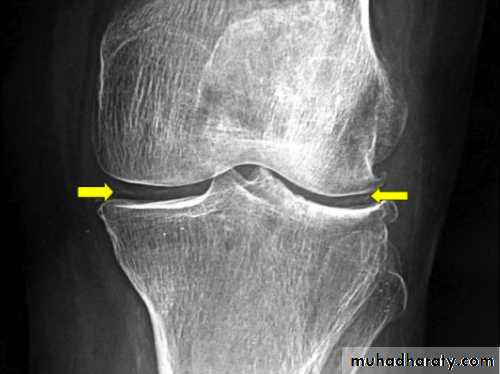

Radiographic Studies

In an appropriate clinical setting, plain radiographs may be supportive of a particular diagnosis.

The findings of chondrocalcinosis and osteoarthritic changes suggest, but do not prove, these diagnoses without corresponding synovial fluid analysis.

In acute polyarthritis, radiographs lack specificity and usually only show soft tissue swelling and intra-articular fluid.

In chronic inflammatory polyarthritis, marginal joint erosions are seen earliest in the small joints of the hands, wrists, and feet in patients with RA.

Chronic gout can also cause erosions with an overhanging edge that typically involve small peripheral joints such as the first MTP joint.